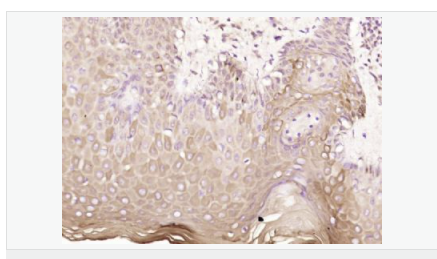

| 產品應用 | WB=1:500-2000 ELISA=1:5000-10000 IHC-P=1:100-500 IHC-F=1:100-500 ICC=1:100-500 IF=1:100-500 (石蠟切片需做抗原修復) not yet tested in other applications. optimal dilutions/concentrations should be determined by the end user. |

| 產品介紹 | Machado-Joseph disease, also known as spinocerebellar ataxia-3, is an autosomal dominant neurologic disorder. The protein encoded by this gene contains (CAG)n repeats in the coding region, and the expansion of these repeats from the normal 13-36 to 68-79 is one cause of Machado-Joseph disease. There is a negative correlation between the age of onset and CAG repeat numbers. Alternatively spliced transcript variants encoding different isoforms have been described for this gene. [provided by RefSeq, Sep 2009] Function: Interacts with key regulators (CBP, p300 and PCAF) of transcription and represses transcription. Acts as a histone-binding protein that regulates transcription. Acts as a deubiquitinating enzyme. Subcellular Location: Nucleus matrix. Predominantly nuclear, but not exclusively, inner nuclear matrix. Tissue Specificity: Ubiquitous. DISEASE: Defects in ATXN3 are the cause of spinocerebellar ataxia type 3 (SCA3) [MIM:109150]; also known as Machado-Joseph disease (MJD). Spinocerebellar ataxia is a clinically and genetically heterogeneous group of cerebellar disorders. Patients show progressive incoordination of gait and often poor coordination of hands, speech and eye movements, due to degeneration of the cerebellum with variable involvement of the brainstem and spinal cord. SCA3 belongs to the autosomal dominant cerebellar ataxias type I (ADCA I) which are characterized by cerebellar ataxia in combination with additional clinical features like optic atrophy, ophthalmoplegia, bulbar and extrapyramidal signs, peripheral neuropathy and dementia. The molecular defect in SCA3 is the a CAG repeat expansion in ATXN3 coding region. Longer expansions result in earlier onset and more severe clinical manifestations of the disease. Similarity: Contains 1 Josephin domain. Contains 3 UIM (ubiquitin-interacting motif) repeats. SWISS: P54252 Gene ID: 4287 Database links: Entrez Gene: 4287 Human Entrez Gene: 110616 Mouse Omim: 607047 Human SwissProt: P54252 Human SwissProt: Q9CVD2 Mouse Unigene: 532632 Human Unigene: 271914 Mouse Unigene: 42932 Rat Important Note: This product as supplied is intended for research use only, not for use in human, therapeutic or diagnostic applications. |